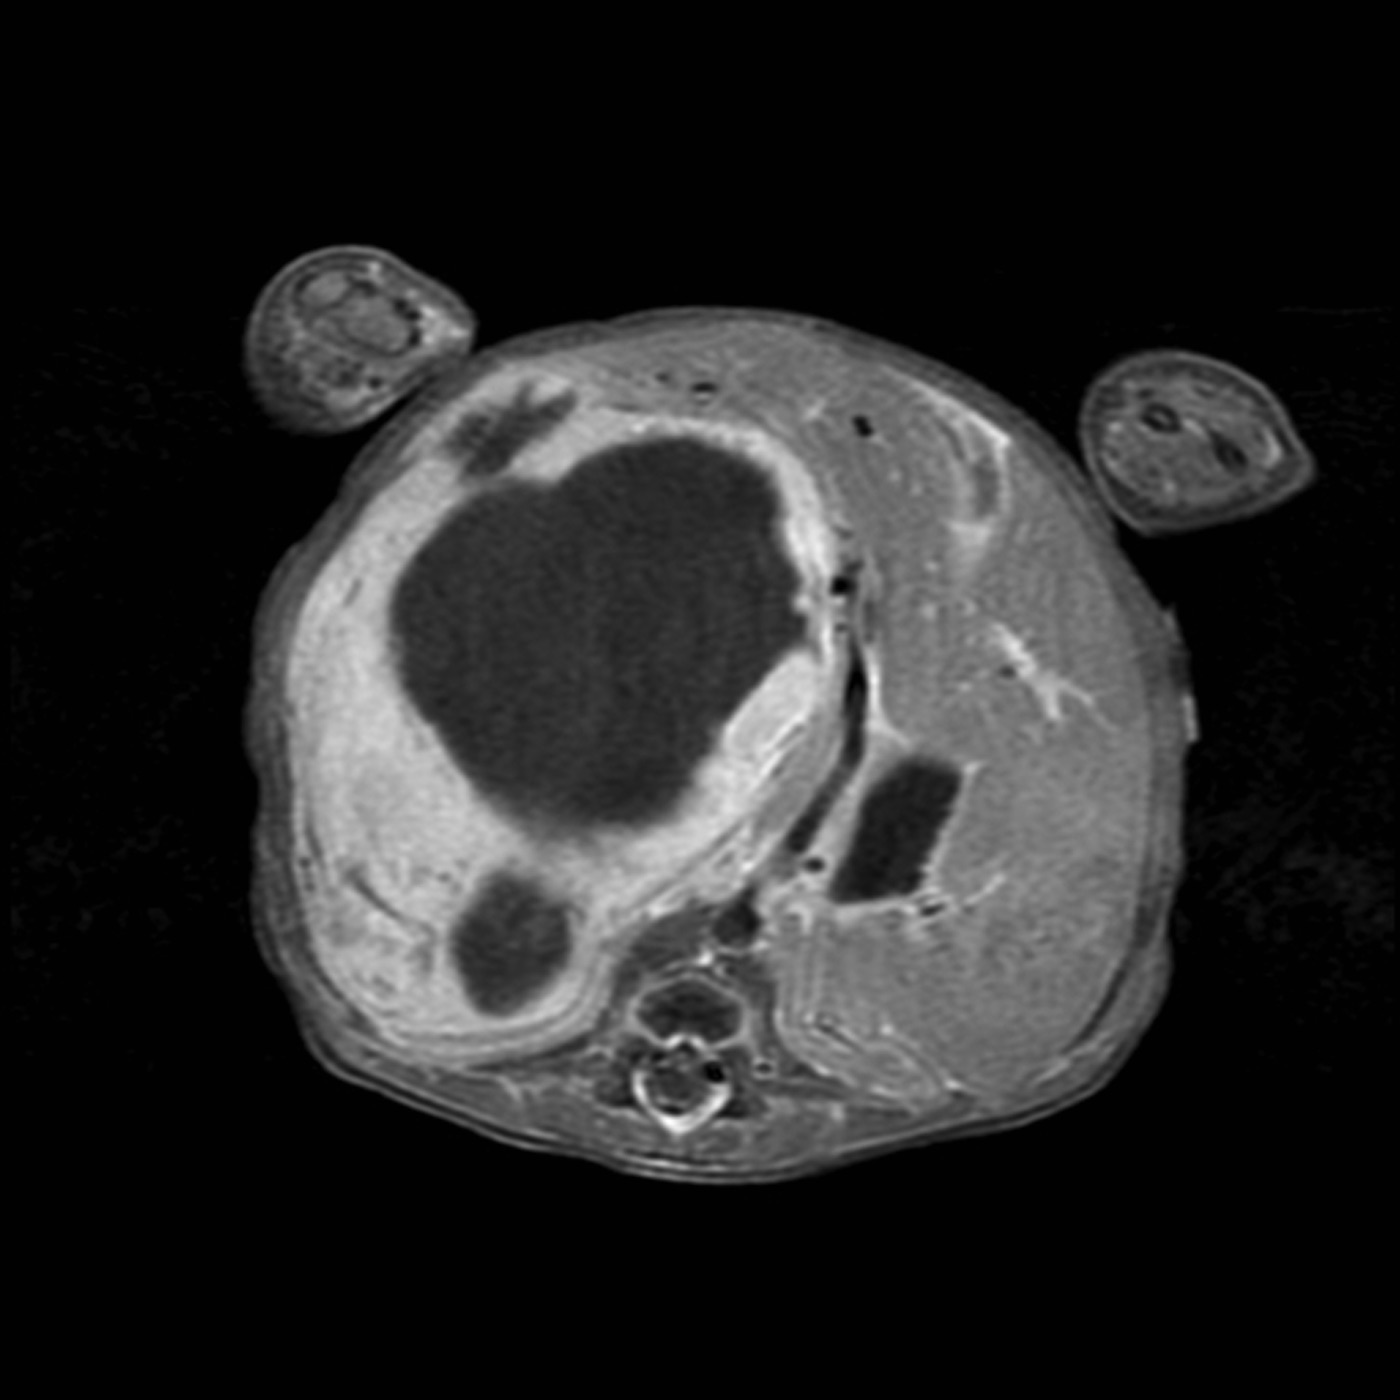

The radiograph showed a large radiopaque mass that encompassed most of the right and left upper quadrants, with multiple loops of bowel displaced into the pelvis, a paucity of bowel gas, and low lung volumes. Abdominal CT revealed a heterogeneous mass with origin in the right lobe of the liver and contact of the left tip of the liver with the spleen (Figure 1). Further evaluation with MRI showed a heterogeneous mass of 8.8 × 6.9 × 8.4 cm with peripheral enhancement and large, nonenhancing areas centrally (Figure 2).

Figure 2 – An MRI scan shows the heterogeneous mass with peripheral enhancement and large, nonenhancing areas centrally.